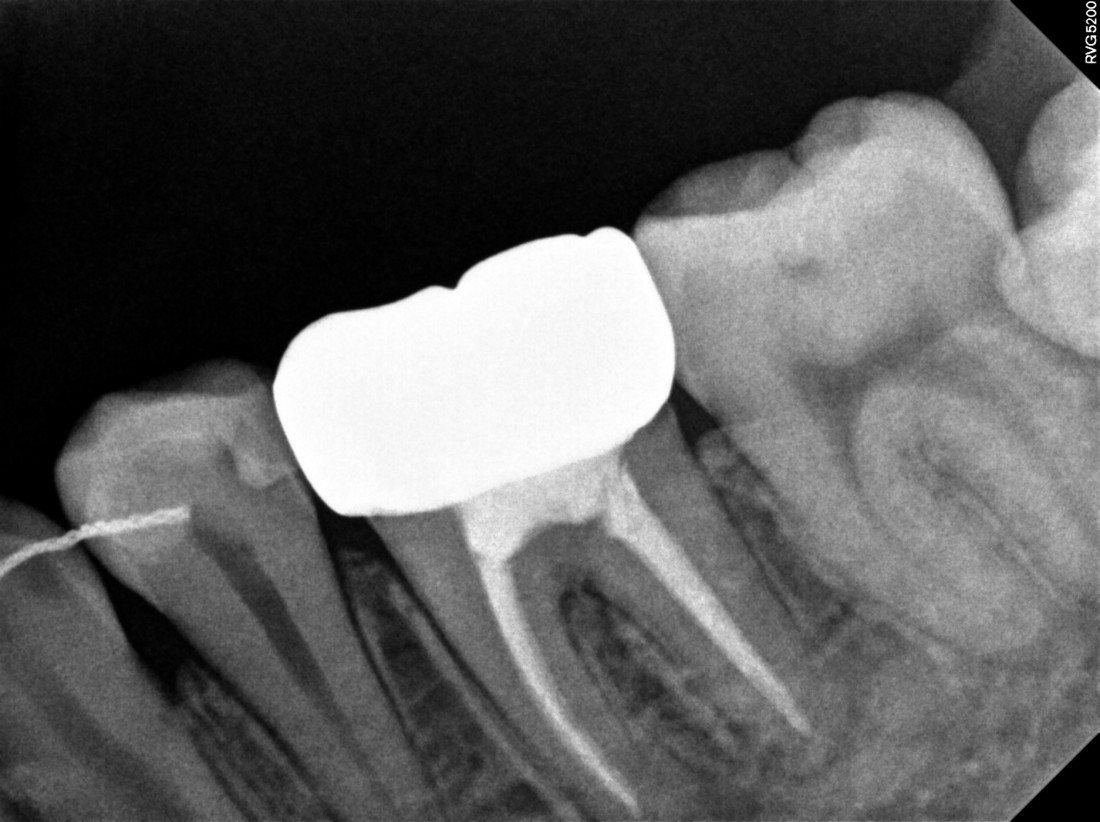

광주 성인 교정치과에서

충치치료와 교정진료를 동시에 받으신

성인 여성 환자분의 케이스입니다.

충치치료 전에는 은색 보철물이 있던 자리에

교정진료의 마무리와 동시에

치아색 보철물을 씌워서

치아교정 + 충치치료를 동시에 진행하였습니다.

광주 성인 치아교정의 경우

충치치료의 시기를 잘 판단하여

성공적인 진료를 완성할 수 있기 때문에

분과별 전문의가 협진하는

광주 성인 교정치과를 선택하시는 것이 좋습니다.